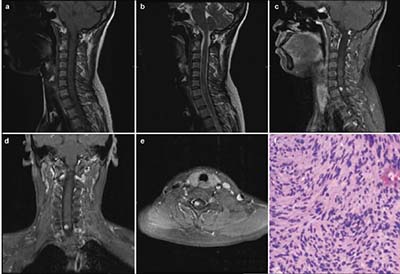

20171023160911  Figure 1 (a) Sagittal T1-weighted magnetic resonance image demonstrating an isointense lesion. (b) Sagittal T2-weighted magnetic resonance image demonstrating a slightly hyperintense lesion, with swelling surrounding it. (c–e) Sagittal, coronal, and axial T1-weighted magnetic resonance images, with gadolinium contrast, demonstrating homogeneous enhancement of the tumor. The tumor appears as a solid mass, located to the right side of spinal cord, with clear margins. (f) Hematoxylin and eosin staining from the biopsy of the mass showing bipolar spindle cells with nuclei arranged in a palisade pattern (Hematoxylin & Eosin stain; magnification, ×100).